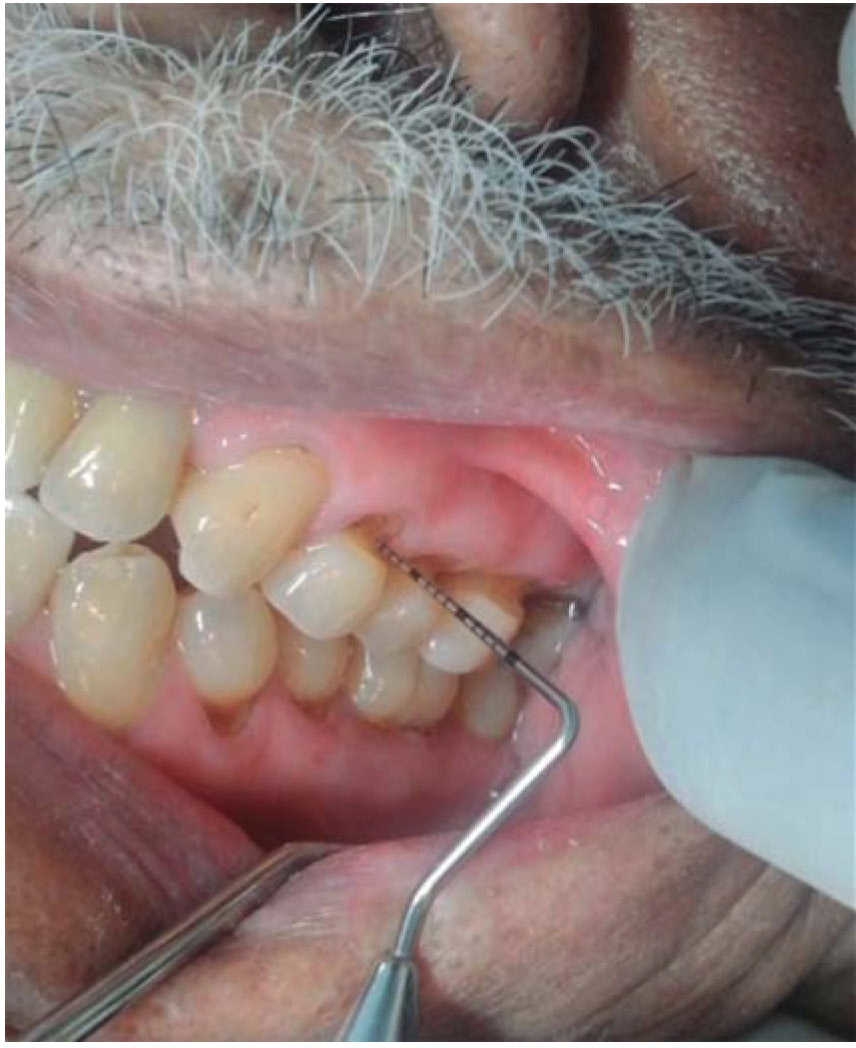

Tanto los tejidos duros como los suaves son importantes en los seres humanos y ante cualquier factor o factores que produzcan un cambio en ellos, afectan la integridad de su estructura y función. En los órganos dentarios se puede manifestar una lesión por pérdida del tejido duro en la unión amelocementaria ya sea en vestibular o lingual, pudiéndose acompañar generalmente de sensibilidad dentinaria. A esta entidad de origen no infeccioso se le llama abfracción (Figura 1), causada por fuerzas oclusales excéntricas que llevan a la flexión dental,1,2 cuya sinonimia actual corresponde a stress flexural, stress tensil o a síndrome de compresión por ser la lesión la evidencia de un conjunto de signos (pérdida de estructura dentaria en forma de cuña y la fractura y el desprendimiento reiterado de restauraciones) así como síntomas (hipersensibilidad dentinaria), cuando la lesión está en actividad.2

Figura 1 Paciente masculino de 60 años de edad con presencia de abfracciones en áreas posterosuperior y posteroinferior. Mérida, Yucatán, México. 2014.